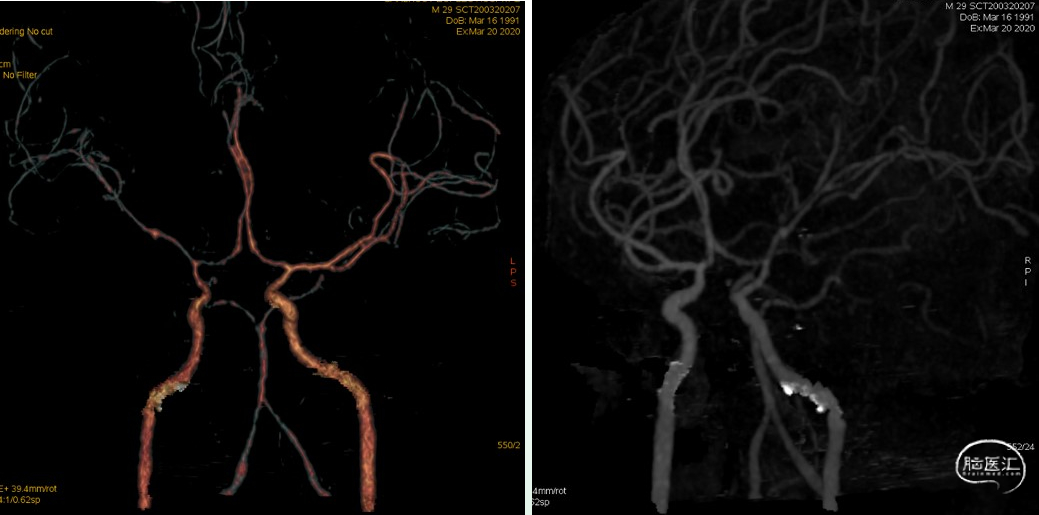

血管造影影像

3、头颅DSA检查——血管造影的最佳检查时机仍有争议。金属类异物强烈散射,CTA效果不佳,根据异物穿通范围、位置及临床表现,必要时行头颅DSA检查。